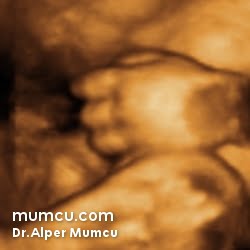

3 Boyutlu ultrason resimleri

Bu sayfadaki fotoğraflar degişik zamanlarda ve farklı hastalarda Dr. Alper Mumcu tarafından çekilmiştir.

8 haftalık gebelik